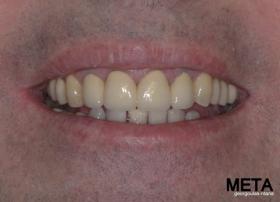

Ο ασθενής  προσήλθε στο ιατρείο μας θέλοντας να βελτιώσει την εμφάνιση των πρόσθιων δοντιών του και να αποκαταστήσει την υγεία κ την λειτουργία όλου του στόματος. Πραγματοποιήθηκε περιοδοντική θεραπεία κ ενδοδοντικές θεραπείες (απονευρώσεις) όπου κρίθηκε απαραίτητο και στη συνέχεια τοποθετήθηκαν 3 εμφυτεύματα, 2 δεξιά στις θέσεις του πρώτου κ δεύτερου γομφίου κ 1 αριστερά στη θέση του πρώτου προγομφίου. Κατά την  τοποθέτηση των 2 εμφυτευμάτων της δεξιάς πλευράς, πραγματοποιήθηκε κλειστή ανύψωση ιγμορείου με το σύστημα Piezotome-Intralift , τεχνική που εξασφαλίζει τη μικρότερη δυνατή επέμβαση κ τη μικρότερη μετεγχειρητική ταλαιπωρία (minimally invasive), καθώς κ αυξητικους παράγοντες PRF. Σε όλη τη διάρκεια της θεραπείας  ο ασθενής ήταν καλυμμένος τόσο αισθητικά όσο και λειτουργικά με προσωρινές μεταβατικές αποκαταστάσεις. 4 μήνες μετά την  τοποθέτηση των εμφυτευμάτων κ την οστεοενσωμάτωσή τους, ακολούθησε η τοποθέτηση των μόνιμων αποκαταστάσεων.